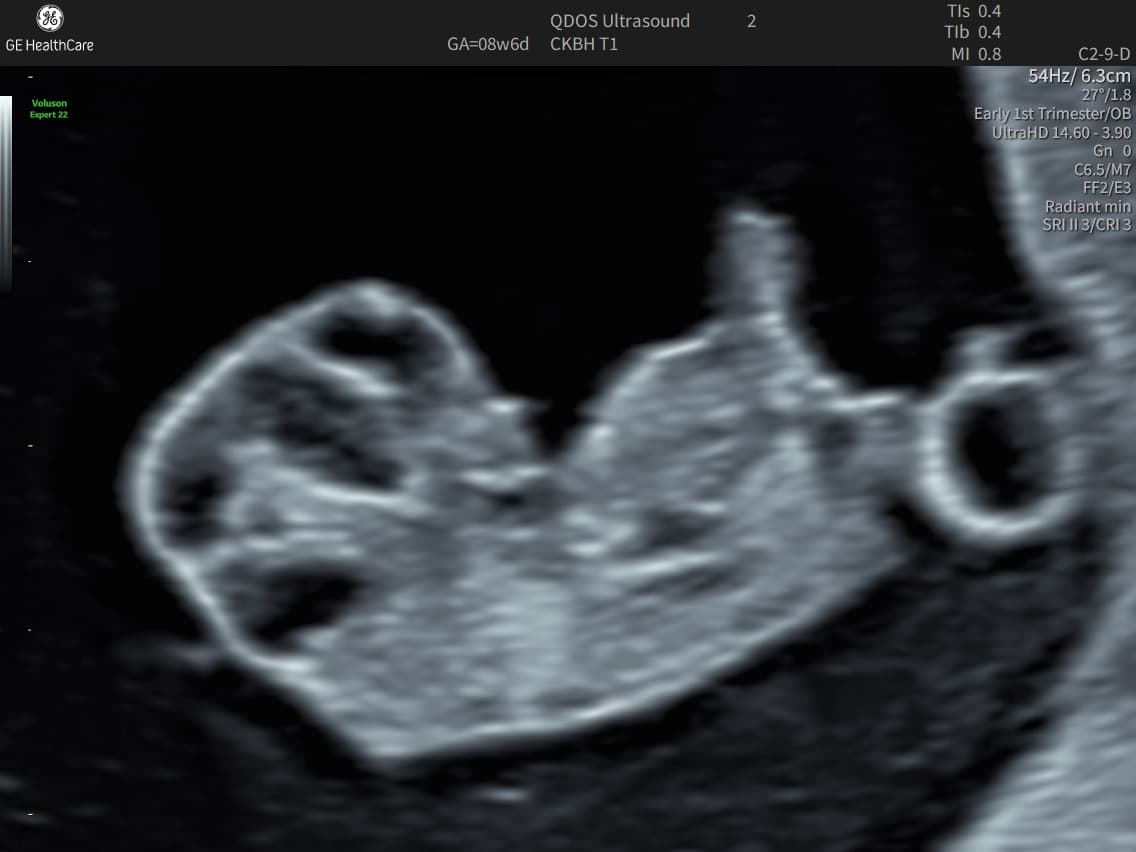

What An Early Pregnancy Ultrasound May Be Able To Detect

• Determine how far along you are and provide an estimated due date.

• Confirm that your pregnancy is progressing as expected and that the baby is in the right place.